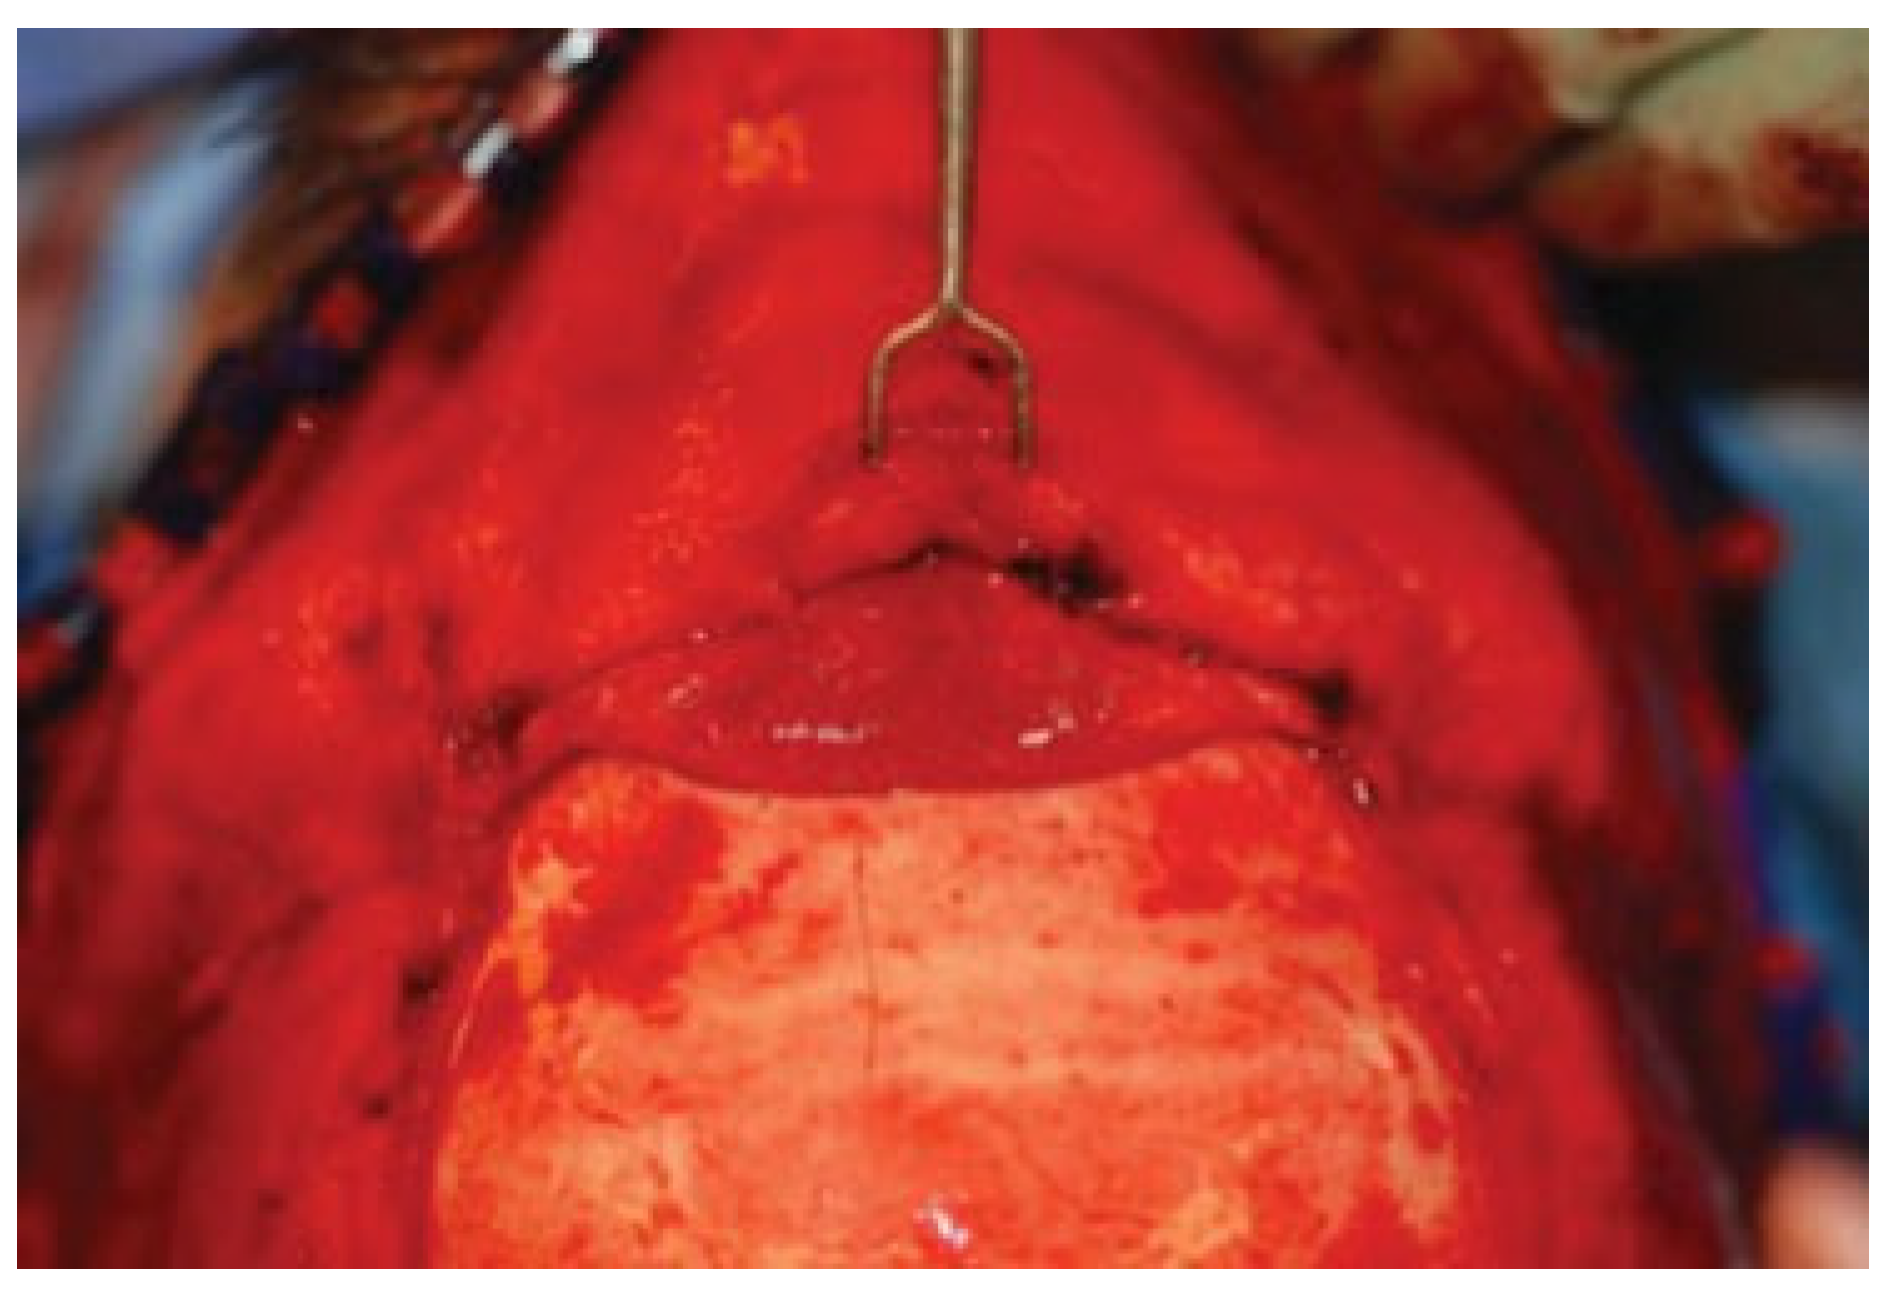

Figure 3. Superior view demonstrating designation of broad-based pericranial flap incorporating supratrochlear vessels. Lines demarcate the planned pericranial flap cuts.

A rectangular pericranial flap pedicled on the supratrochlear vessels is designed (Figure 3) and incised with electrocautery, followed by elevation with a Cottle elevator. Through the external rhinoplasty approach, the nasal skin and soft-tissue envelope is then elevated superiorly in the subcutaneous plane and connected to the superior dissection. The tunnel is widened to 3 cm at the nasofrontal area appropriately and the flap passed through this into the nasal cavity (Figure 4 and Figure 5). The narrowest point is at the nasal dorsum at approximately 2 cm. Intra-operative laser angiography with the SPY system is performed to verify distal perfusion of the flap (Figure 6).